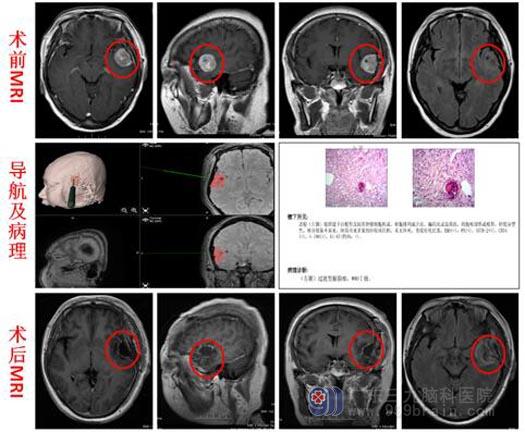

在广东三九脑科医院综合神经外科进一步头颅MRI检查发现:1.左侧颞部占位性病变,大小约30mm×29mm×24mm,考虑脑膜瘤可能性大,待排颅内孤立性纤维瘤;2.空泡蝶鞍。

排除手术禁忌症后,由鲁明副院长主刀,在全麻下行“左颞脑膜瘤切除术”,见肿瘤,质硬,血供丰富,予显微镜下整块全切除,肿瘤与脑组织界限较清,术腔严格止血,手术顺利。术后病理:过渡型脑膜瘤,WHO I级。